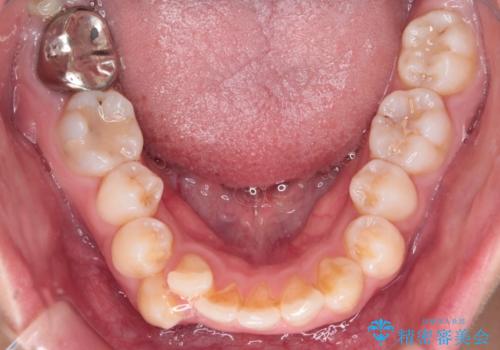

- 前歯から奥歯にかけて歯の重なりが激しい歯のがたつき(重度叢生)を主訴にご来院されました。精密検査の結果、歯が並ぶスペースが大幅に不足しており、歯並びを整え、口元を美しく引っ込めるためには、スペースの確保が必要と診断しました。そこで、上下左右の第一小臼歯(4番目の歯)を計4本抜歯し、そのスペースを利用して歯並び全体を整える抜歯矯正の治療計画を立案。装置には、透明で目立たないインビザラインを採用し、審美性と治療効果の両立を目指しました。

今回の治療では、重度の叢生を改善するため、まず計画通り上下左右4本の小臼歯を抜歯し、歯を並べるための十分なスペースを確保しました。装置には透明で取り外し可能なインビザラインを使用。抜歯によってできたスペースを最大限に活用し、マウスピースを定期的に交換しながら、デコボコを解消しつつ、前歯を効果的に後退させました。

治療の結果、長年の悩みであった重度の歯のがたつきが解消され、口元の突出感も改善。機能的にも安定し、審美的にも美しい、理想的な歯並びを獲得していただけました。